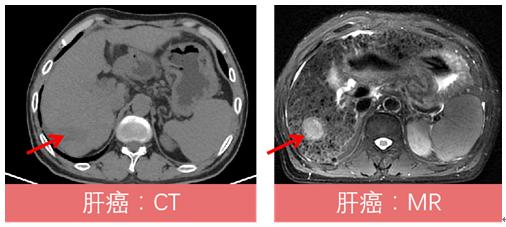

4、由于MR对人体组织的显示比CT更清晰,因此PET/MR在骨骼肌肉系统疾病、头颈部肿瘤、颅内肿瘤、乳癌、肝癌、椎管内肿瘤、骨髓病变等方面具有优势。